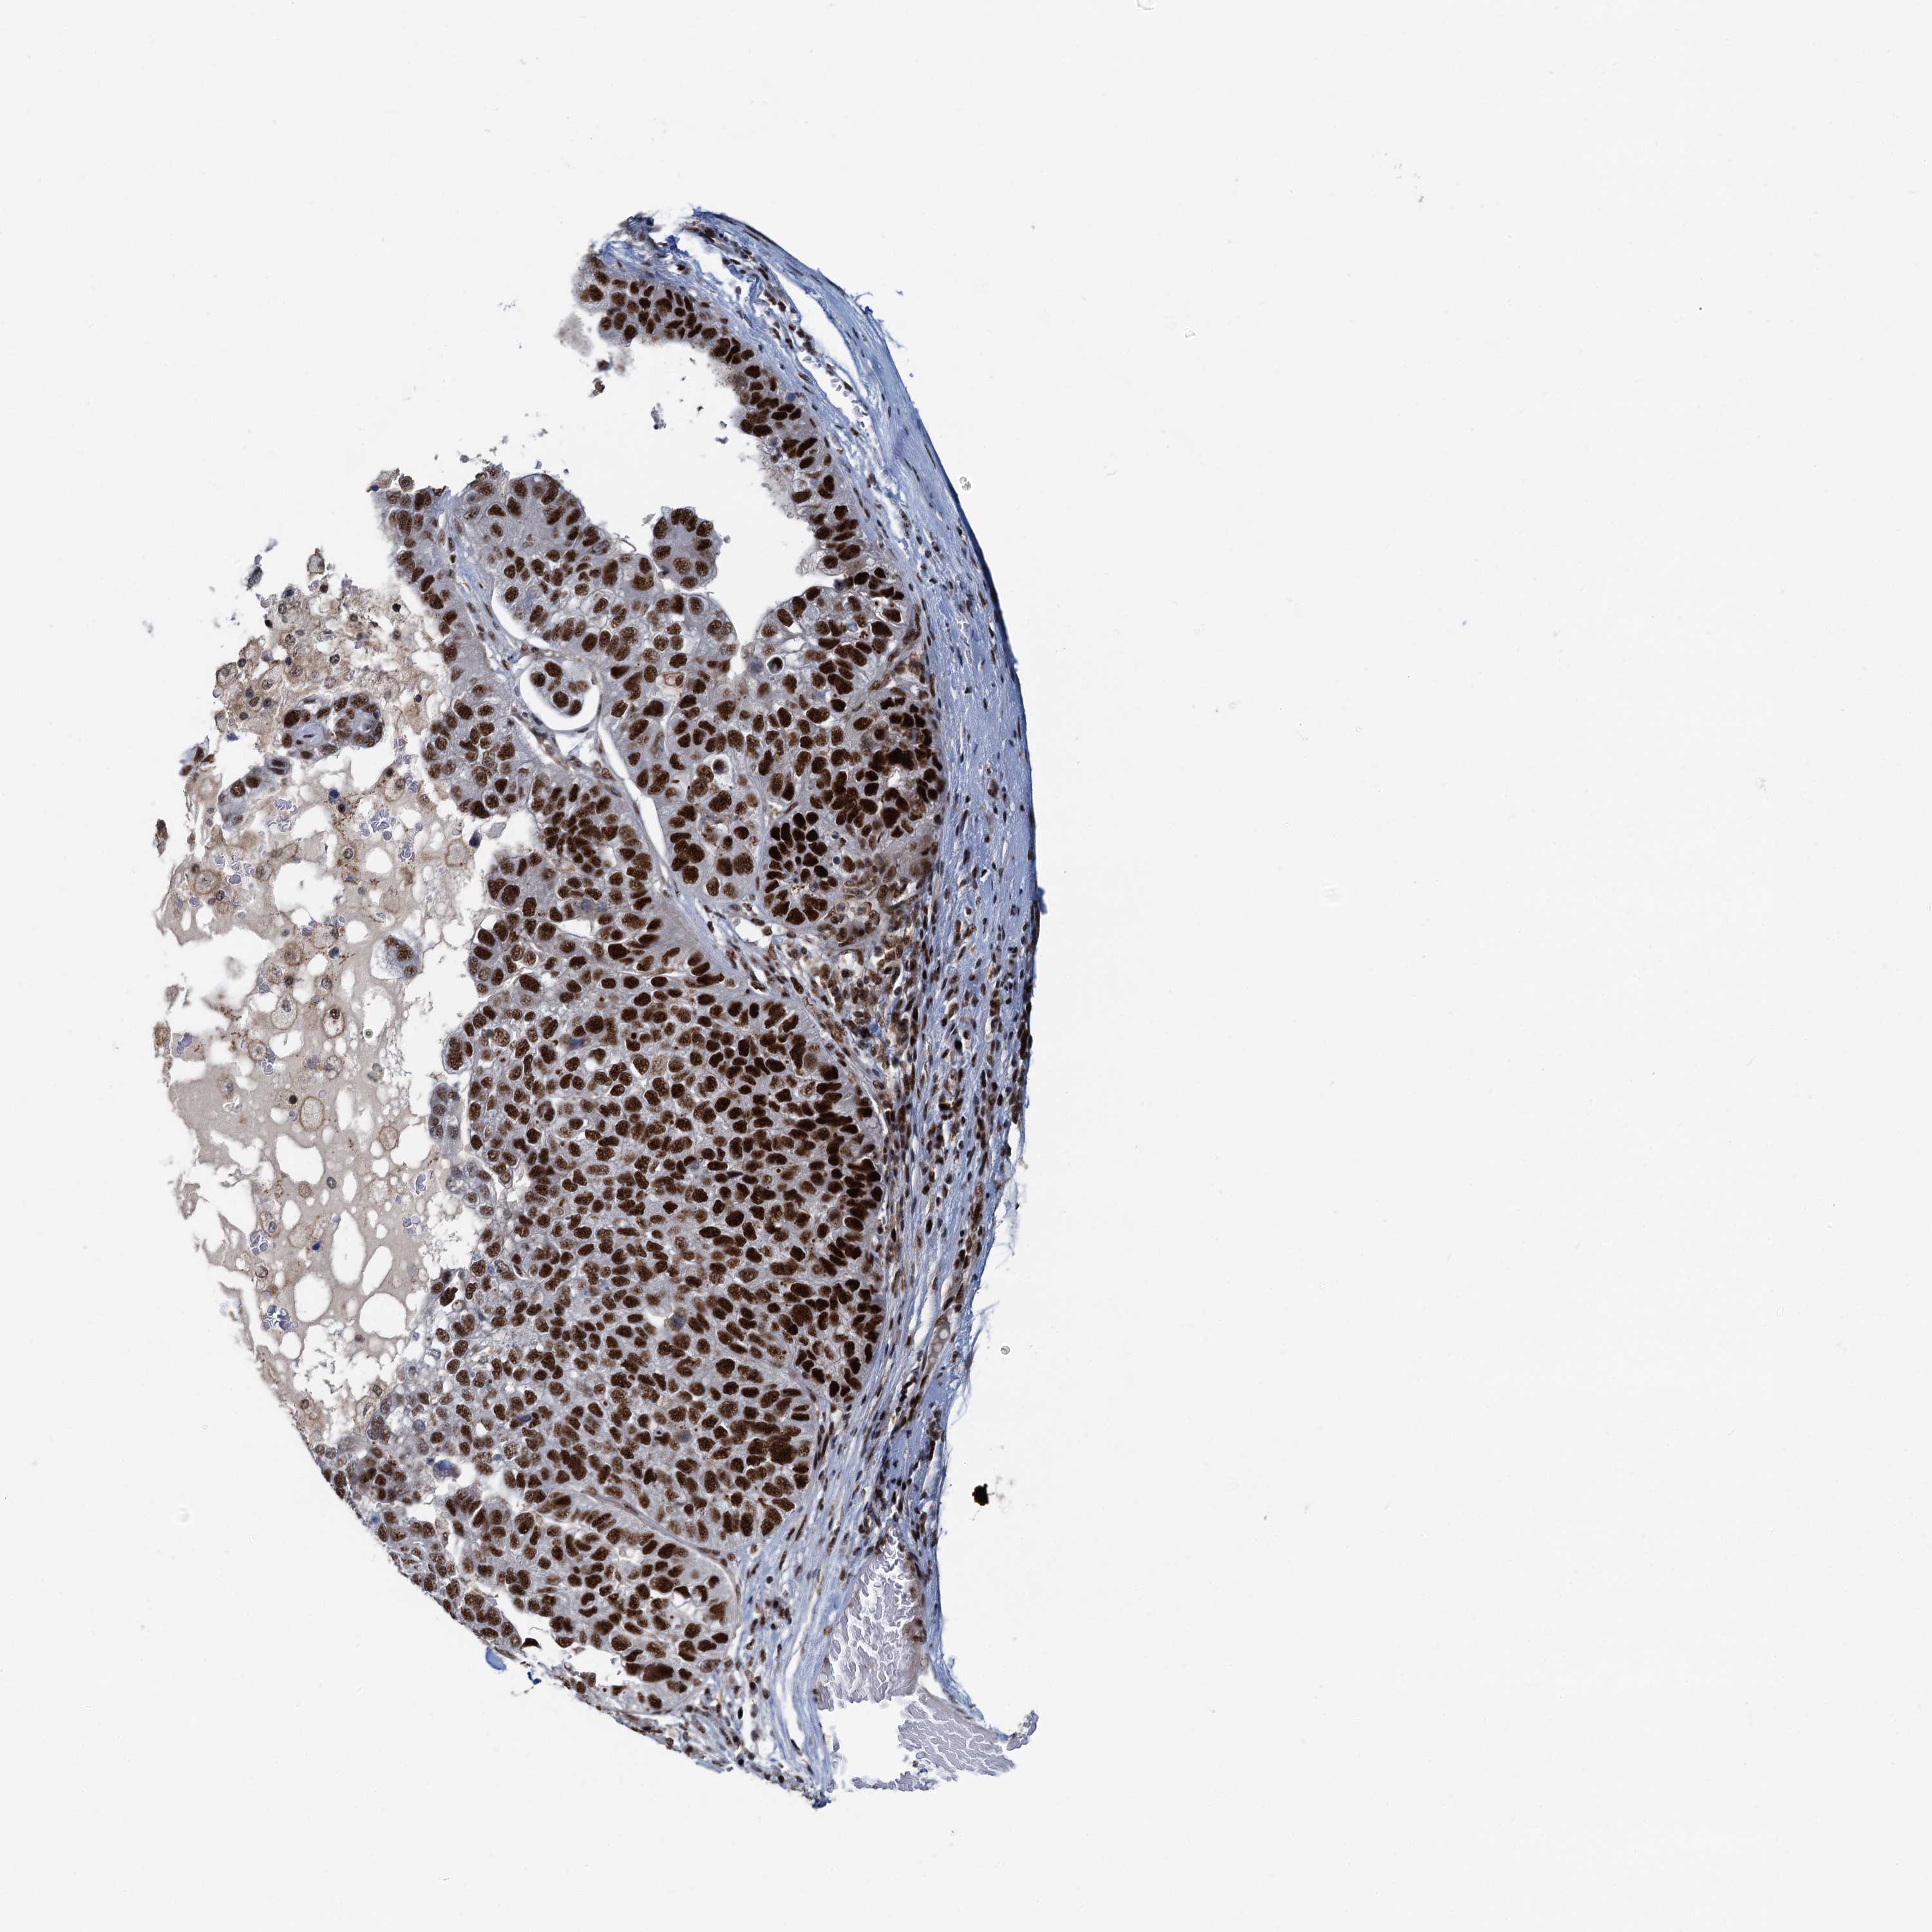

PANCREATIC CANCER - Protein expressioni

A mouse-over function shows sample information and annotation data. Click on an image to view it in a full screen mode. Samples can be filtered based on level of antibody staining by selecting one or several of the following categories: high, medium, low and not detected. The assay and annotation is described here.

Note that samples used for immunohistochemistry by the Human Protein Atlas do not correspond to samples in the TCGA dataset.

Antibody stainingi

Antibody staining in the annotated cell types in the current human tissue is reported as not detected, low, medium, or high, based on conventional immunohistochemistry profiling in selected tissues. This score is based on the combination of the staining intensity and fraction of stained cells.

Each image is clickable and will lead to virtual microscopy that enables deeper exploration of all samples and also displays staining intensity scores, fraction scores and subcellular localization as well as patient and tissue information for each sample.

Antibody HPA040252

Staining

High

Medium

Low

Not detected

Intensity

Strong

Moderate

Weak

Negative

Quantity

>75%

75%-25%

<25%

None

Location

Nuclear

Cytoplasmic/membranous

Cytoplasmic/membranous,nuclear

Adenocarcinoma, NOS